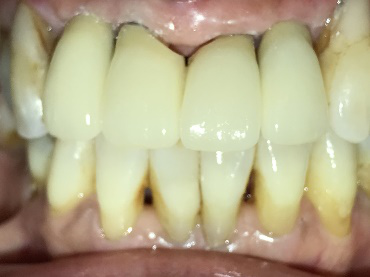

レントゲンで詳しく診てみると、虫歯が歯根のほうまで進行し、保存することができないことがわかり、抜歯しました。抜歯後、骨が大きく欠損していましたので、骨造成を行いインプラントを2本埋入しました。

所感

抜歯後の欠損したところを補う方法には、部分入れ歯、ブリッジ、インプラントがあることを説明したところ、自分の歯と同じような感覚で嚙むことができるインプラントを選択されました。この方は、2016年に右下にインプラント治療をし、インプラントの良さを十分に理解しておられましたので、今回も2本歯を失ったところにインプラント治療を希望されました。今回もX-Guideを使った埋入で、安心安全に行うことできました。

Before

【抜歯後】

After